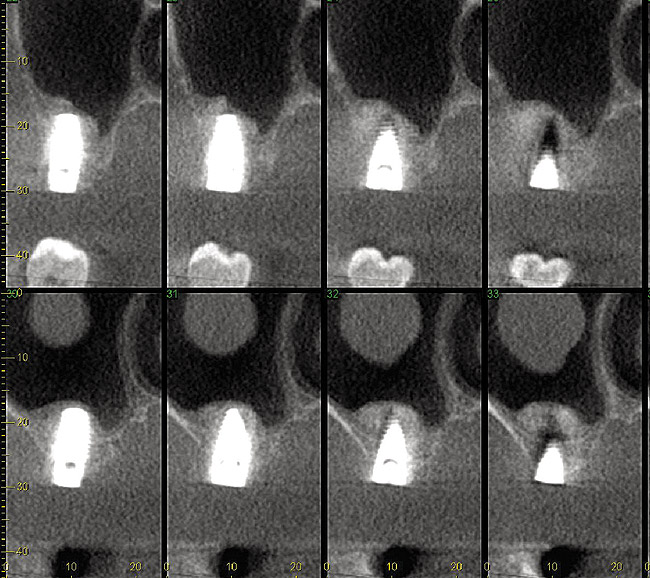

Fig 12. Cone-beam computed tomography 6 months after the procedure reveals the bony mantle covering the inserted implants.

Figure 12